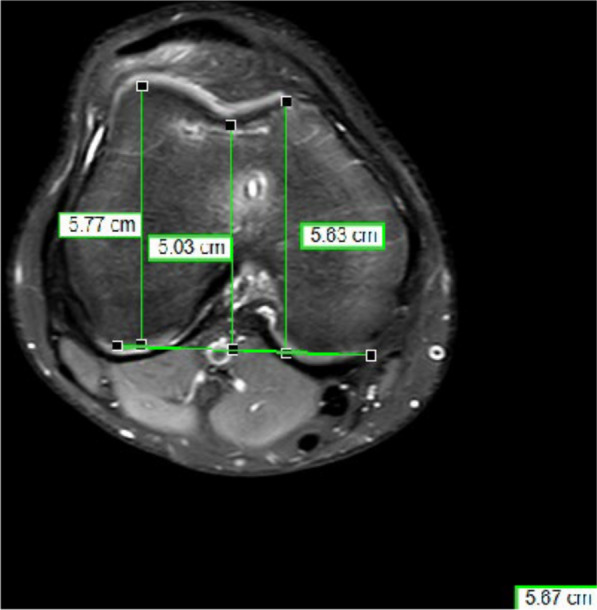

Methods: A total of 83 trochleoplasties in 83 patients were performed between 2014 and 2021 in one institution. Surgical indications for trochleoplasty were recurrent patellofemoral instability and a lateral trochlear inclination angle (LTI) ≤ 11˚ and a trochlear depth ≤ 6 mm. Of the trochleoplasties, 40 were done by open technique (OT) and 43 by arthroscopic technique (AT). In every case an additional medial patellofemoral ligament (MPFL) reconstruction was performed. Additional tuberosity tibia transfer and/or de-rotation of the femur were done when indicated. Pre- and postoperative magnetic resonance imaging (MRI) were analyzed in respect to LTI, trochlear depth, and lateralization of the patella. Postoperative subjective clinical assessment was done using the Kujala Score, Banff II Score, Tegner Score, and Marx Score.

Results: Of the patients, 15 with OT and 20 with AT were available for follow-up. The mean follow-up was 29.9 months in the OT group and 12.7 months in the AT group. No re-dislocation was observed in either groups. A significant reduction of LTI, increase of trochlear depth, and a reduction of lateralization of the patella was observed between the pre- and postoperative MRI scans in both groups. No significant difference in the observed MRI parameters was found between the two groups. Neither was there a difference in the postoperative Kujala Score, Banff II Score, Tegner Score, and Marx Score between the two groups. Length of stay was on average 6.2 days in the AT group and 8.1 days in the OT group. The surgical time was on average 141 min in the OT group and 160 min in the AT group.